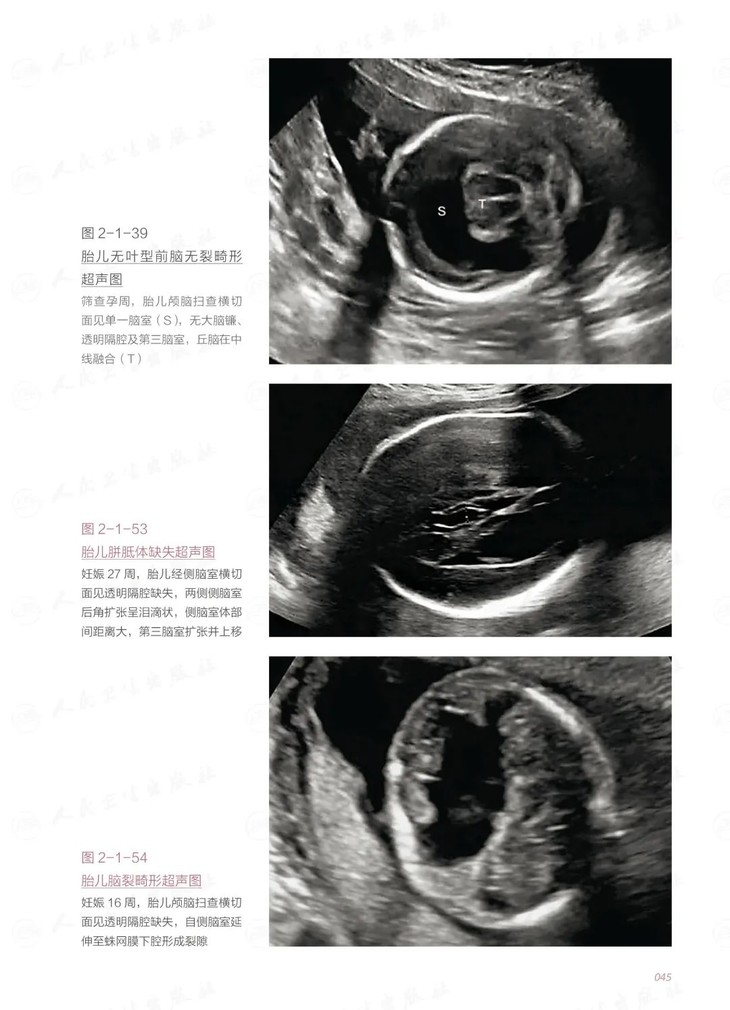

全书共10章,第一章对产前超声的应用进行了概述,第二章至第五章内容按胎儿各个系统划分,第六章介绍了胎儿生长发育的超声评估,第七章至第十章分别描述了胎儿血流动力学、胎儿附属物、孕妇子宫前壁下段剖宫产切口监测及孕妇宫颈的超声检查方法,尽可能全面覆盖筛查孕周可能涉及的疾病和临床相关问题。全书以妇产科超声医师临床工作中面临的实际问题为立足点,详细介绍了标准切面规范化扫查动态、静态扫查方法,重点阐述了胎儿常见异常的超声征象及伴发异常。